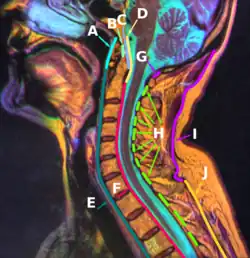

![]() Membrana tectoria, transverse, and alar ligaments. ("Transverse ligament" and "vertical portion" visible intersecting at center.) | |

The cruciate ligament of the atlas consists of the transverse ligament of the atlas, a superior longitudinal band, and an inferior longitudinal band.[1][2] The superior longitudinal band connects the transverse ligament to the anterior side of the foramen magnum (near the basilar part) in the occipital bone of the skull. The inferior longitudinal band connects the transverse ligament to the body of the axis bone (C2).[1]